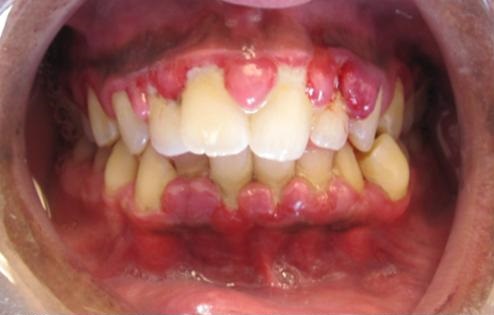

处于第一阶段的异常情形

该异常效应周期的初始阶段通常始于上一次周期结束后的第7天。此时,SCP-CN-2150的牙龈边缘,即牙齿与口腔黏膜交界处的膜龈联合线将首先出现弥散性红肿和点状出血。炎症反应在48小时内迅速加剧,牙龈组织开始出现病理性增生。增生组织首先向牙冠方向的附着龈和游离龈龈顶点扩散,同时龈乳头1显著膨胀,开始填充牙缝。